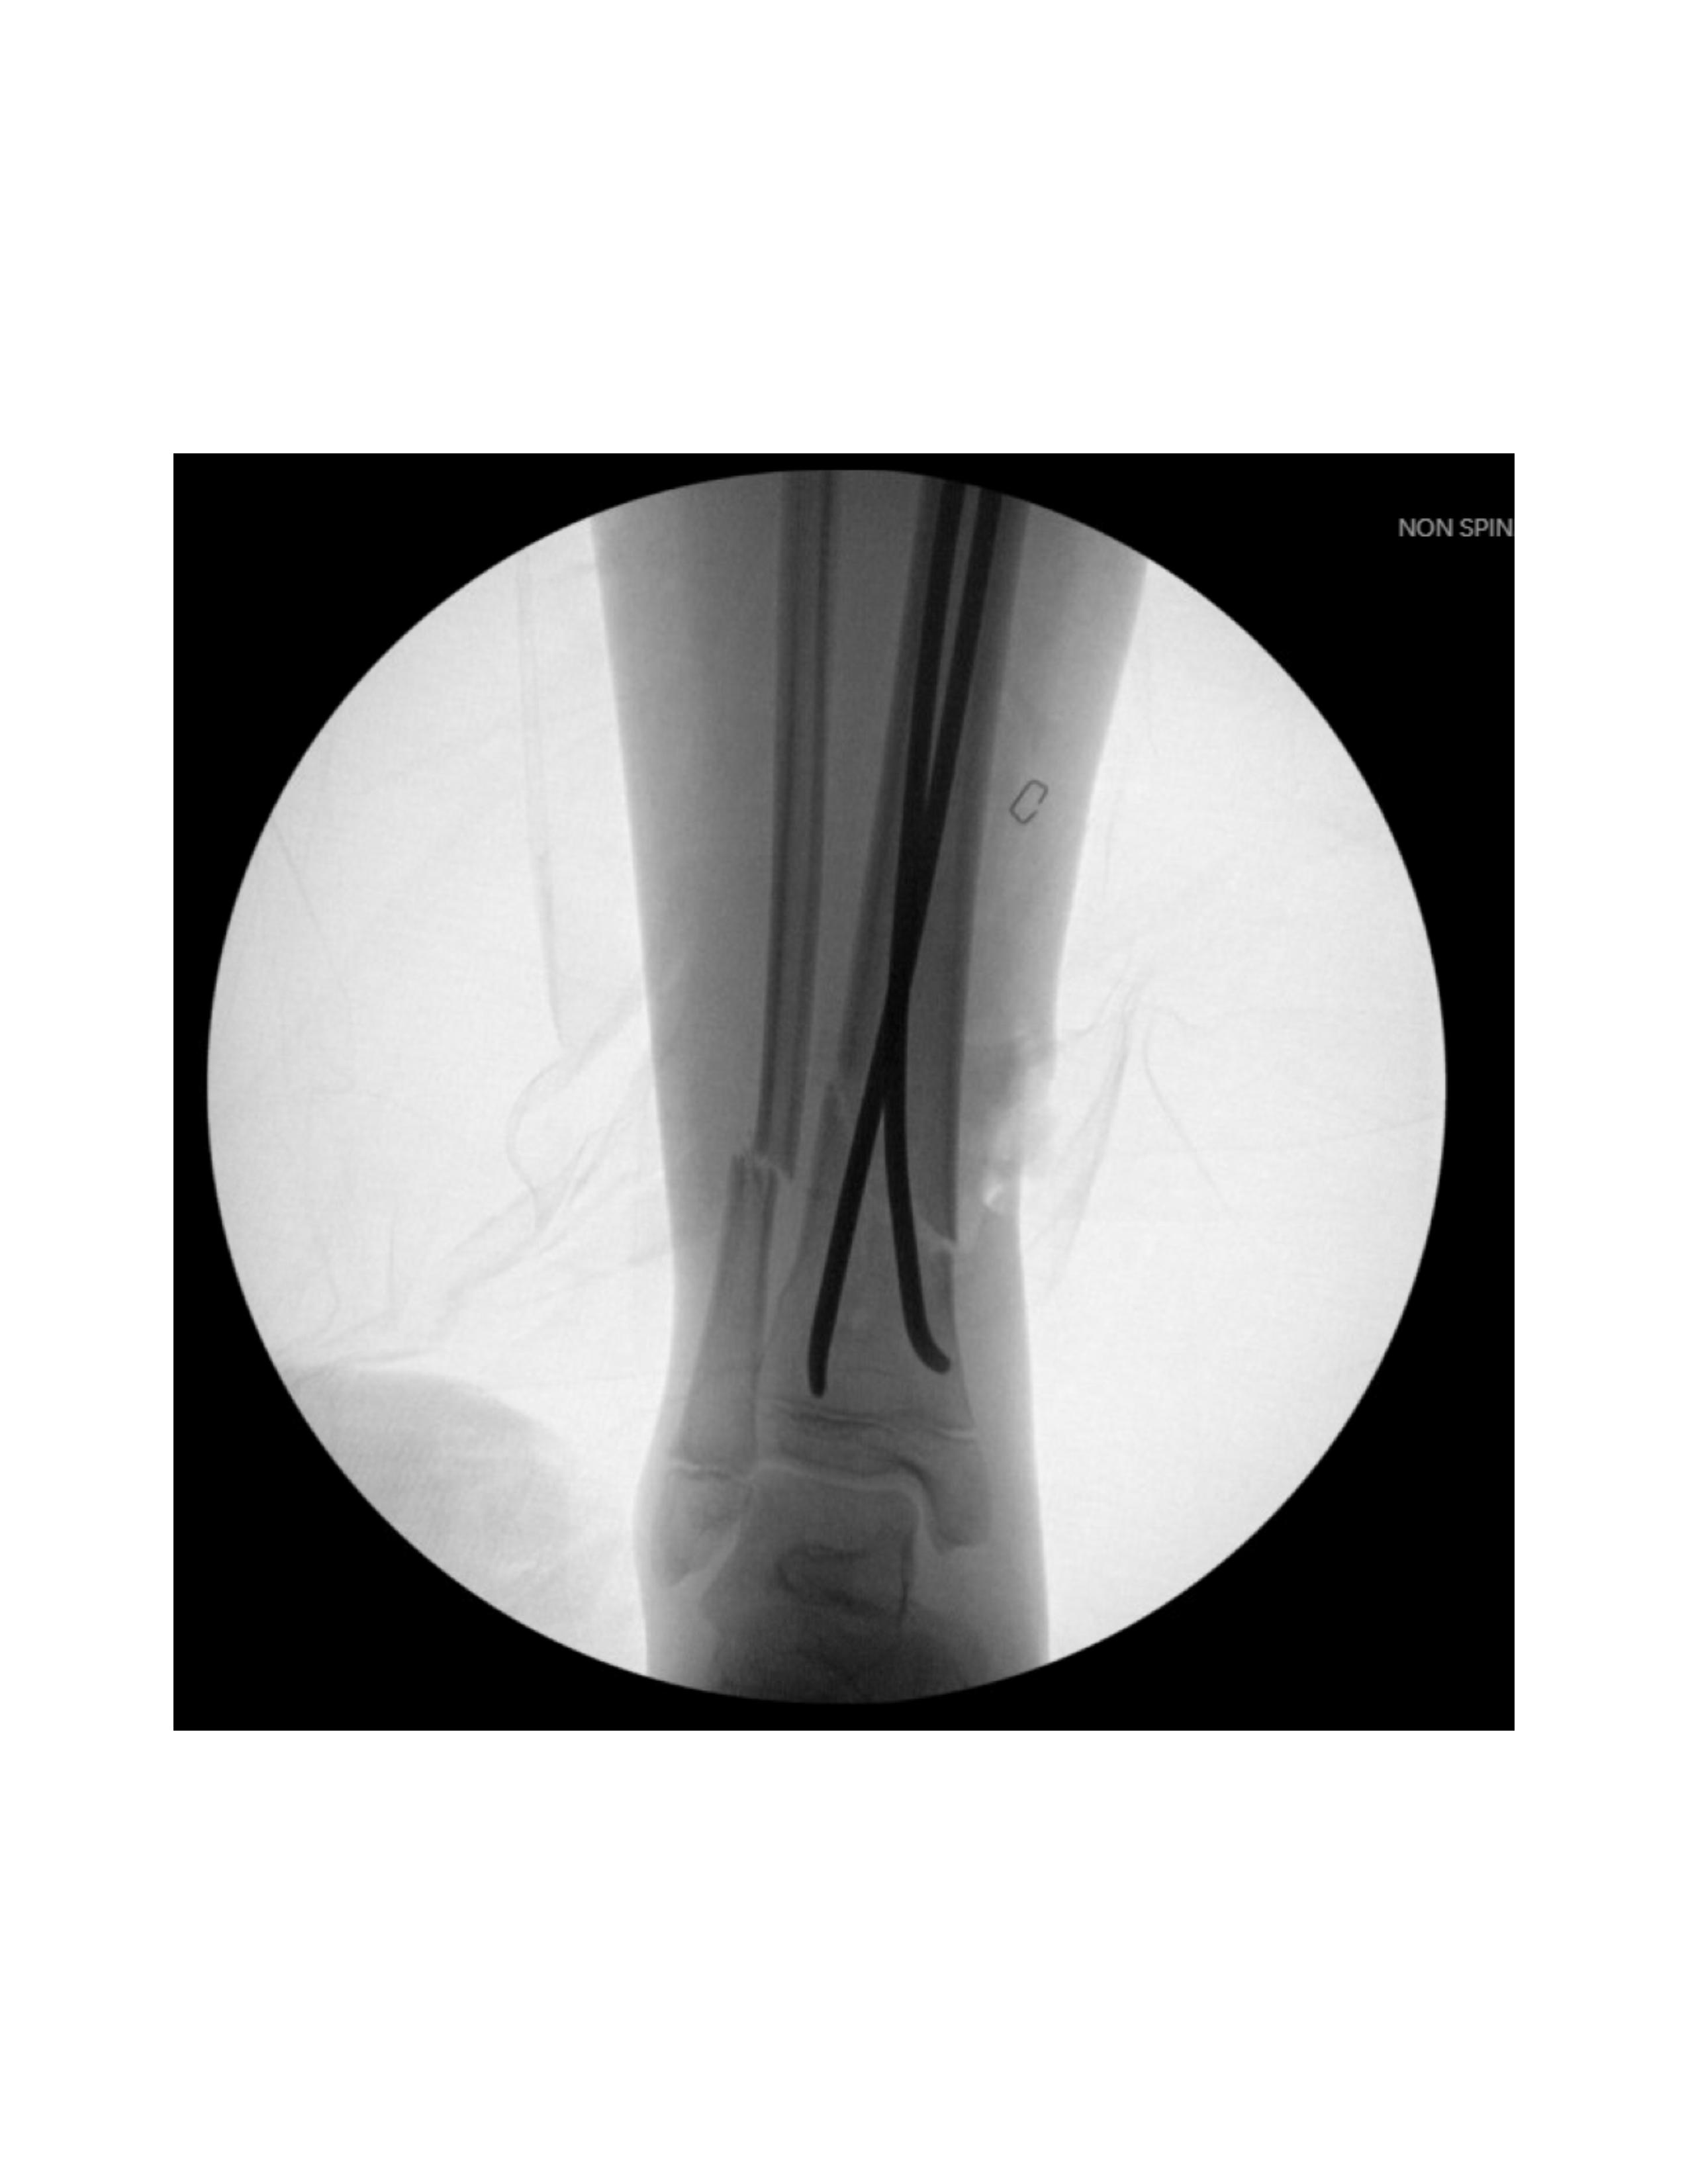

First, fluoroscopy is utilized to identify the fracture site. The mobility of the distal fragment is assessed and a provisional reduction is attempted (Figure 2).

Next, the fracture is manually reduced and both nails are gently advanced past the fracture site by mallet. The curvature of the nails and their tips assists in reducing and stabilizing the fracture, inserted shy of the growth plate. Nail positioning is confirmed by fluoroscopy (Figure 5).

The fracture site is then reassessed under fluoroscopy to confirm maintained reduction. (Figure 8 and Figure 9) Wounds are irrigated and closed in two layers, followed by sterile dressing and short leg splint application.